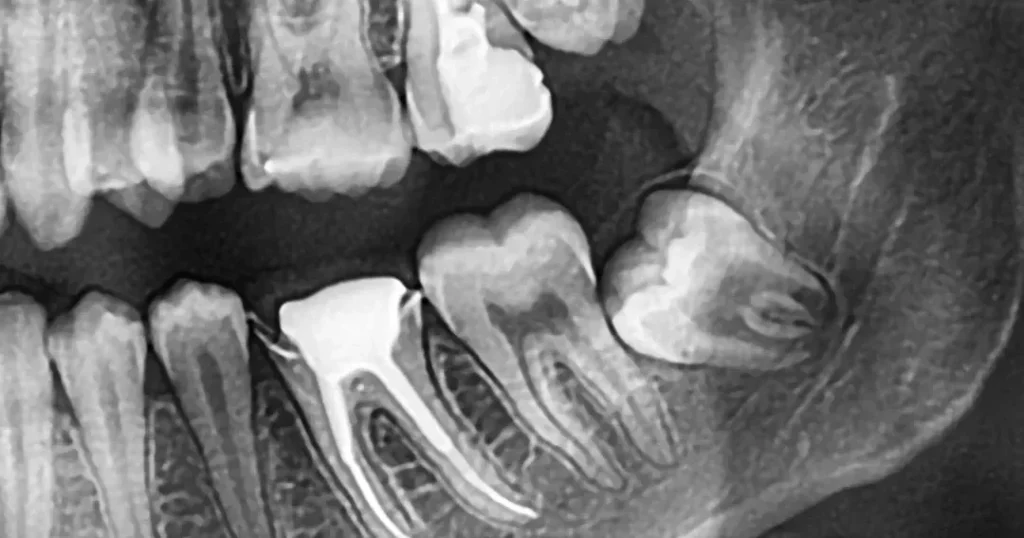

- X線撮影: 必要に応じてレントゲン写真を撮り、骨格や歯根の位置関係をチェックします。